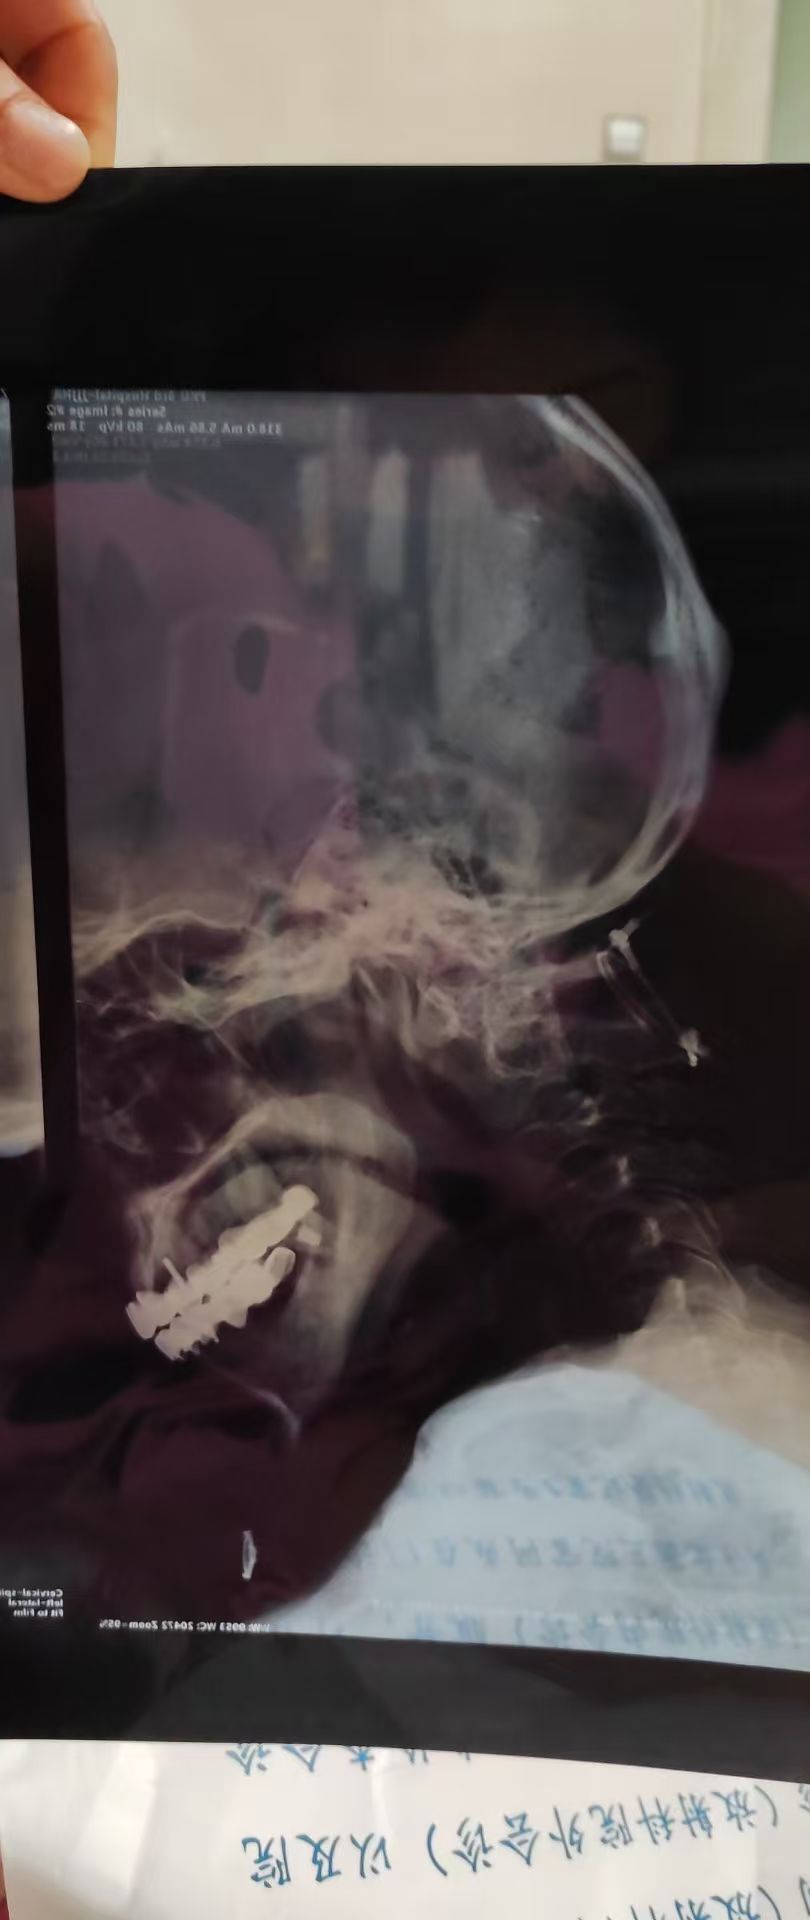

• 术后状况:手术方式是用肽缆把寰枢椎缠上,手术手脚麻木,医生让观察一段时间,一个月后手脚无力,背部僵硬。

• 术后影像: